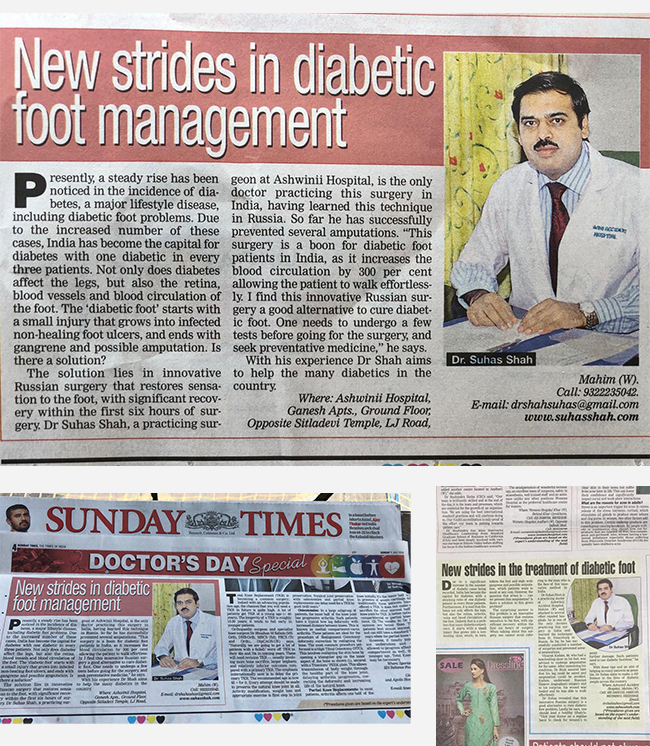

Dr. Suhas Shah has been practicing as an orthopedic surgeon with super specialization in Ilizarov surgery since last 16 years. He is visiting as an Ilizarov specialist all over Maharashtra and has done more than 1400 surgeries in this specialty till now. I have been a faculty member during various Ilizarov courses & workshops held all over India.We now have a center for total Orthopedic care under one roof.

Dr. Suhas Shah is a renowned orthopedic surgeon from India who has extensive experience in using the Ilizarov technique to treat various congenital deformities in children.

Dr. Suhas Shah is an Indian orthopedic surgeon who has made significant contributions to the field of orthopedic surgery, particularly in the area of limb...

At Dr. Suhas Shah Orthopedic Center, we provide comprehensive orthopedic and trauma care under one roof, specializing in advanced techniques like Ilizarov surgery and limb lengthening & reconstruction. With over 16 years of experience, Dr. Suhas Shah has performed more than 1,400 Ilizarov surgeries and serves as a visiting Ilizarov specialist across Maharashtra.